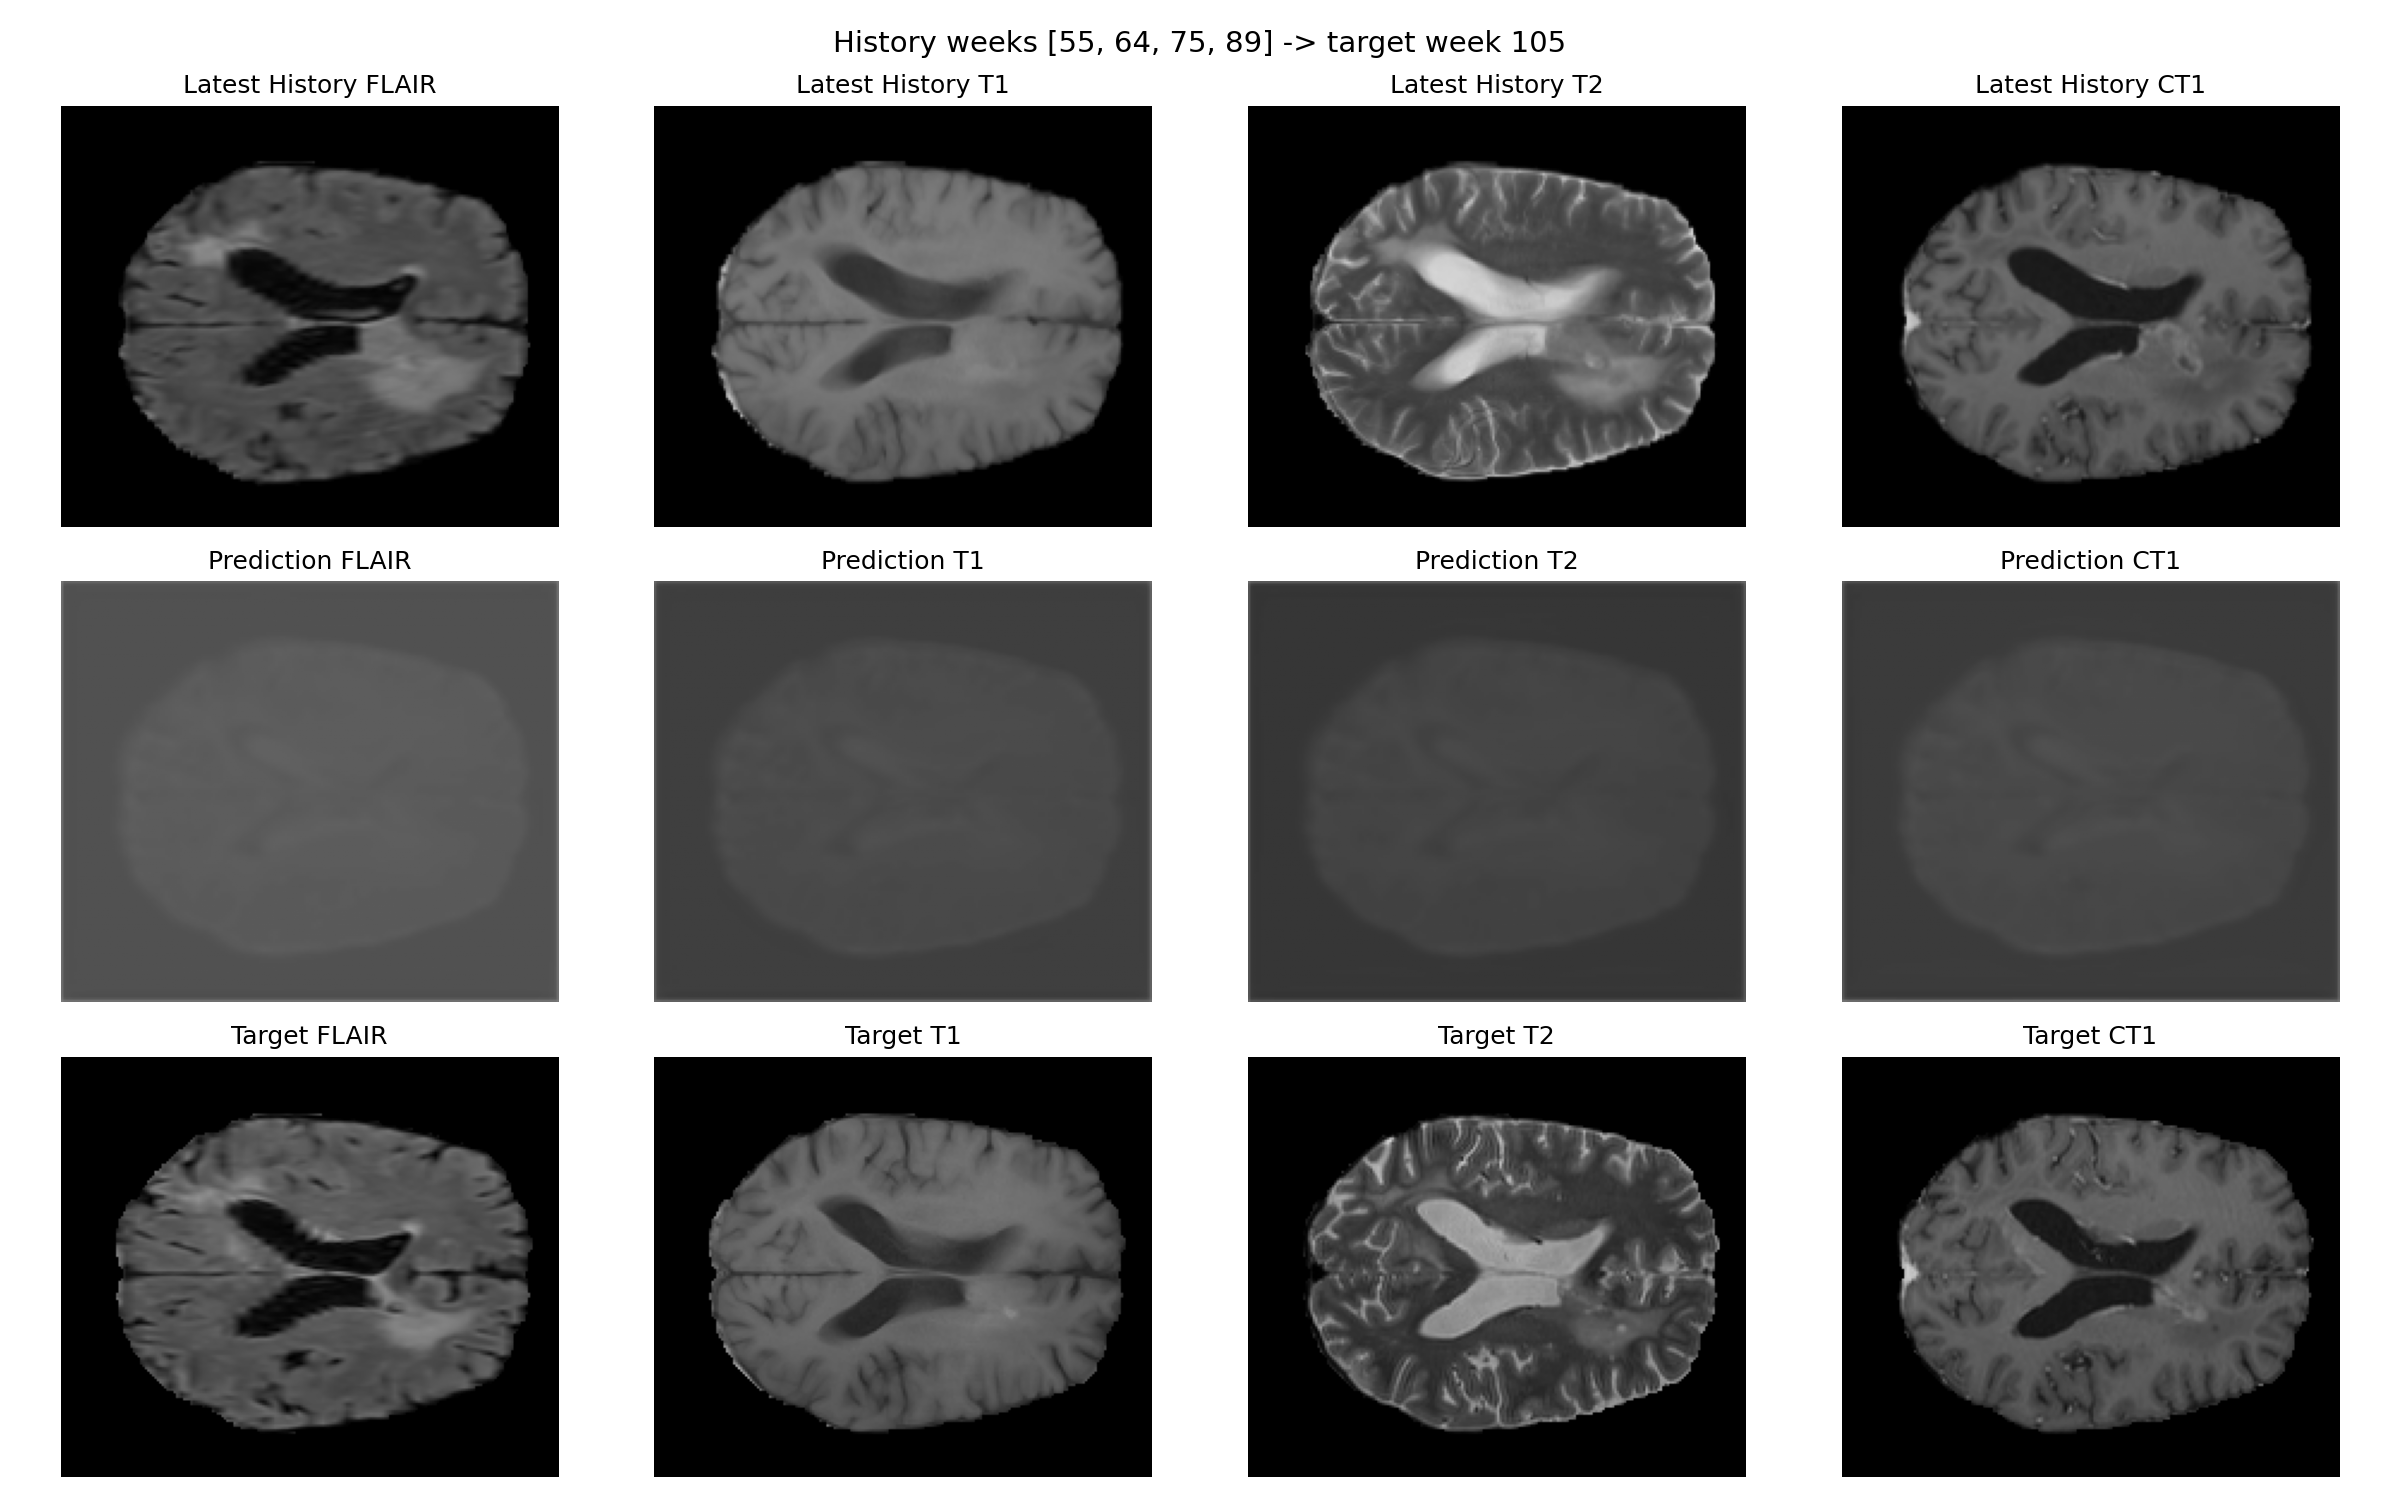

Patient 007

Prediction and target for patient 007

Prediction versus target for week 105.